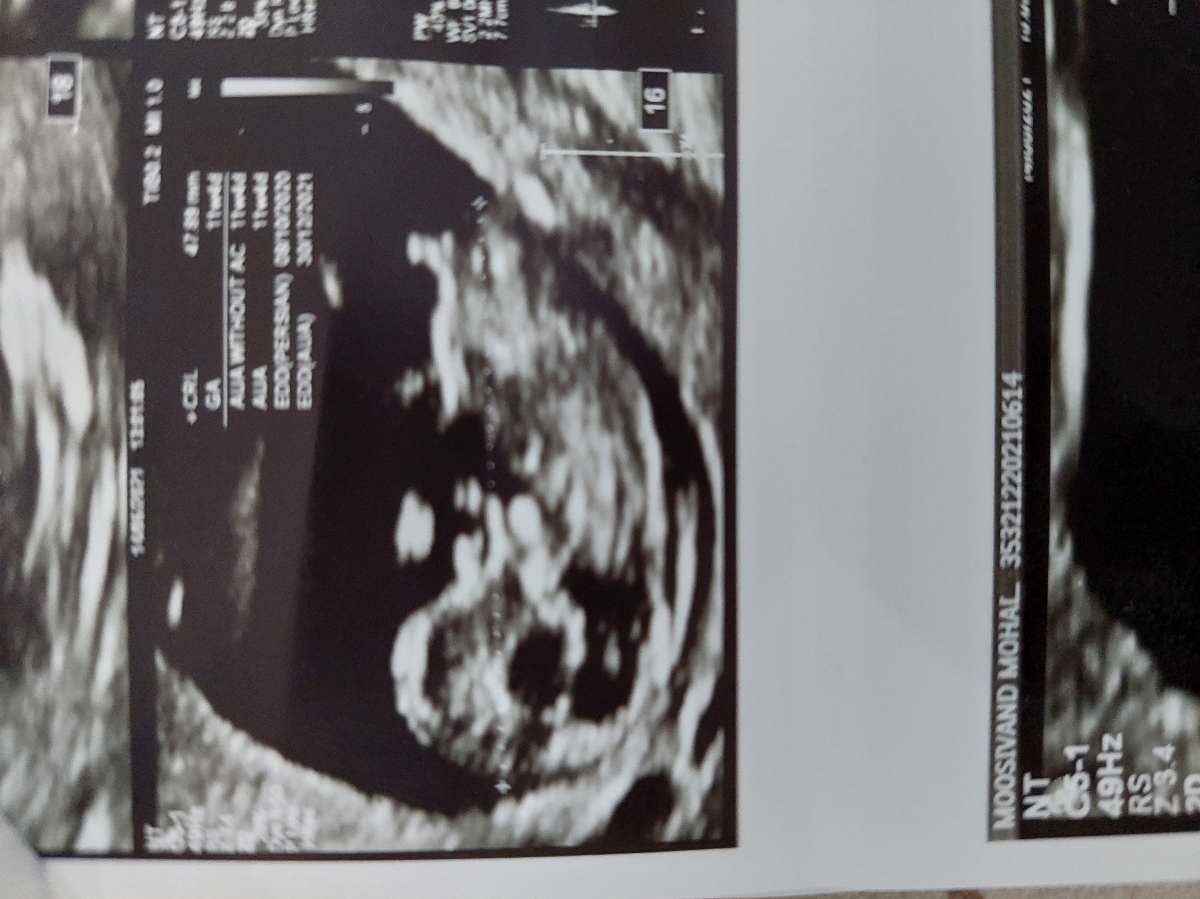

اخه بگم چی دکتر توی سونوگرافی احتنال دختر داد امروز رفتم پیش دکتر خودم که ازمایشمو نشون بدم صدای قلبشو گوش داد گفت احتمال میدم پسره اصلا گیج شدم

از ضربان قلب نمیشه تشخیص داد عزیزم

ولی ان تی هم دقیق نیست

دکتر خودم گفت ضربان قلبش تند میزنه پسره اما سونوگرافی گفت دختر

من ان تی رفتم گفت قطعا پسره آنومالی هم تایید کرد کهپسره معمولا پسرو زودتر تشخیص میدن